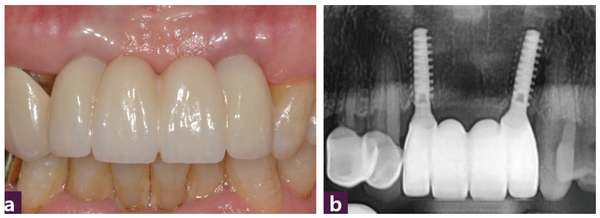

식립 1개월 후 연조직의 양호한 치유 상태와 순측의 풍부한 연조직 sealing을 관찰할 수 있다. 치조제와 치은연의 보존 및 개선도 관찰된다 [그림 10].

식립 2개월 후 zirconia 최종 보철물을 제작해 장착했고 순측의 연조직 형태가 수직적인 재생이 돼 발치 이전보다 개선된 모습을 볼 수 있다. thick gingival biotype으로 개선되면서 연조 직의 형태가 지금보다 더 풍융하게 개선될 것으로 예상된다 [그림 11, 12].

12, 22번 치료 전과 발치 후 즉시 MagiCore를 식립해 최종 보철 장착 후 구강 내 이미지를 비교해 봤다. 중등도 이상의 치주 질환과 gingival recession이 동반된 경우에도 MagiCore를 이용한 최소침습 수술을 통해 환자의 부담은 경감하면서 만족할 수 있는 수준의 치료 결과를 낼 수 있었다 [그림 13].